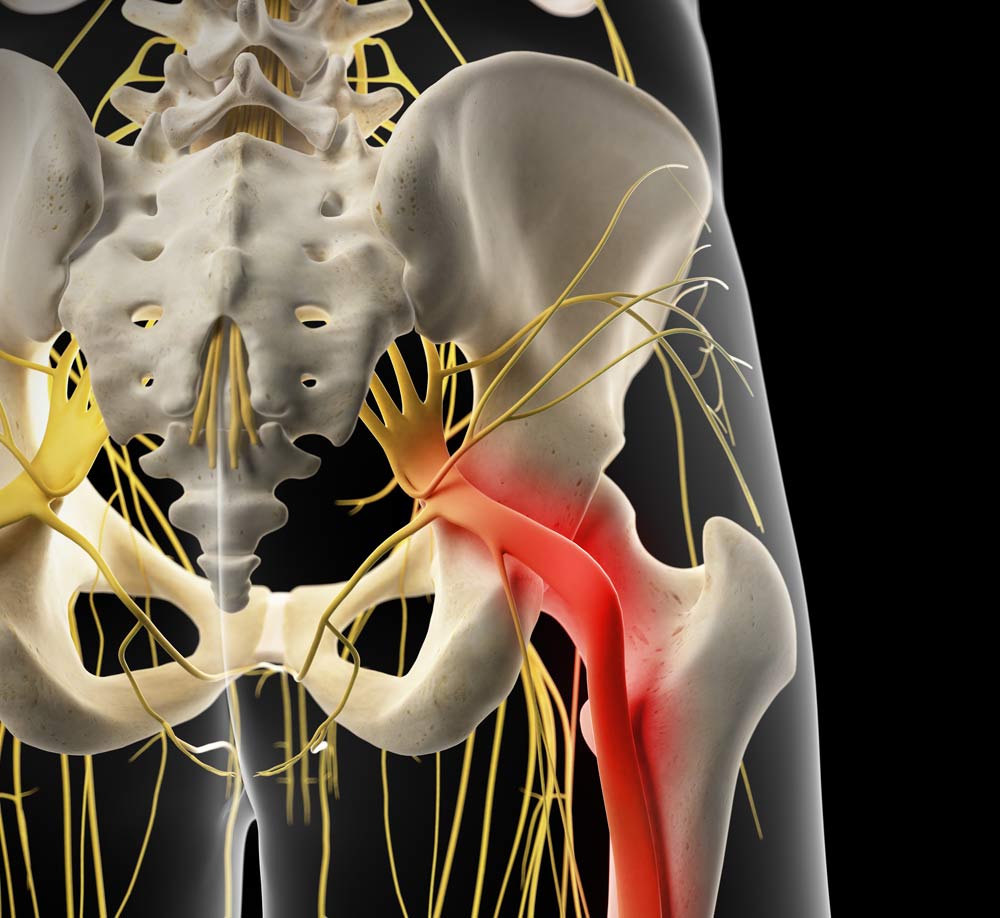

Download Sciatic nerve pain pictures